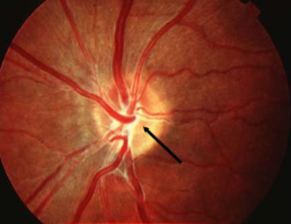

corkscrew prepapillary vascular loop

congenital

appearance:

aberrant development of retinal vasculature system (arterial usually but can be venous)

unilateral vessel loop arising from disc & returning to disc

extends up to 1/3 into vitreous cavity

may be partially enclosed w/ glial tissue

concurrent cilioretinal arteries in 75% of cases

complications:

must r/o acquired loops

rare BRAO/CRAO, TMB, recurrent vitreous hemorrhage, subretinal hemorrhage